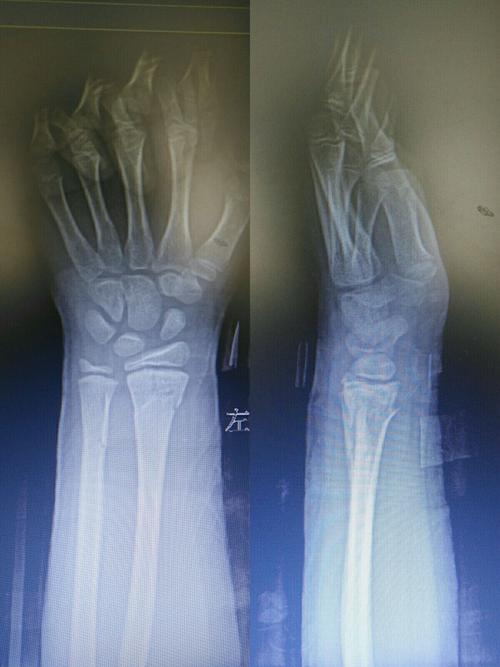

左手桡骨远端骨折图,正常左手桡骨远端图片

复位后拍片:左桡骨远端骨折,对位对线良好.

林莲菊,摔伤左手桡骨远端骨折病例

左桡骨远端骨折图片

左手桡骨远端骨折图片

左侧桡骨远端骨折图片

左尺桡骨远端骨折图片